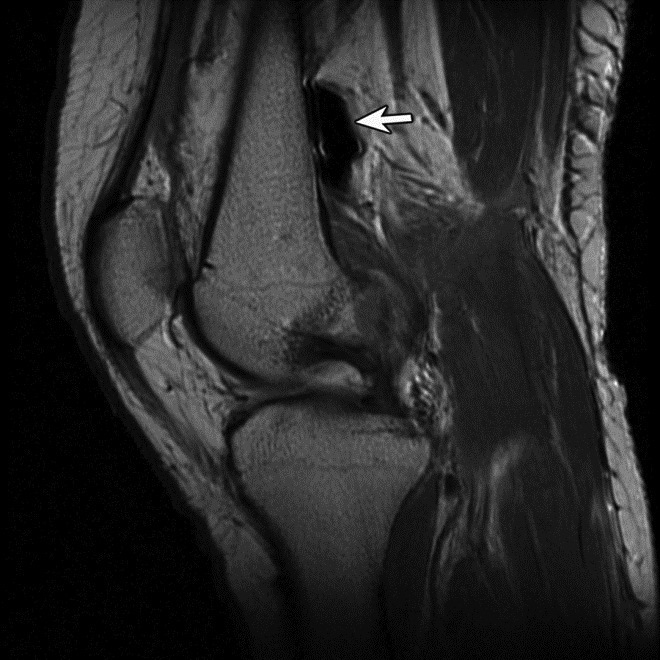

Susceptibility Artifact. (A) Sagittal proton-density-weighted fat-saturated image of the knee shows susceptibility artifact arising from three metallic screws for patellar tendon transfer with obscuration of the patellar tendon insertion and proximal tibial marrow.

(B) Sagittal proton-density-weighted image of the knee shows blooming dark signal (arrow) secondary to intra-articular gas following traumatic arthrotomy. |